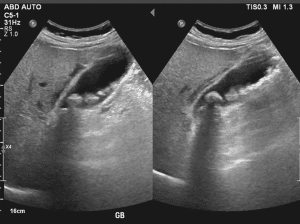

3-Biliary tractÂ

Evidence of gallstone in the gallbladderÂ

Approach to Biliary Tract Ultrasound:Â

Elements of Examination:Â

Gallbladder:Â

Size and Shape: Make sure the size, shape and wall thickness are normal. Ensure that a gallbladder is normally pear shaped.Â

Wall Thickness: Check the wall thickness; if increased one may suspect inflammation (eg cholecystitis).Â

Contents: Attempt to find the presence of stones, sludge and other pathological characteristics.Â

Sonographic Murphy’s Sign: Press with the transducer on the abdomen to determine whether there is tenderness in the gall bladder area to indicate cholecystitis.Â

Common Bile Duct (CBD):Â

Measurement: Diameter of CBD must be measured. Normal diameter ranges from <6mm-8 mm, but it may show variation with age.Â

Patency: Look for renal calculus or kidney stones or any other obstruction. CBD must be dilated as obstruction or cholestasis is suggested by this condition.Â